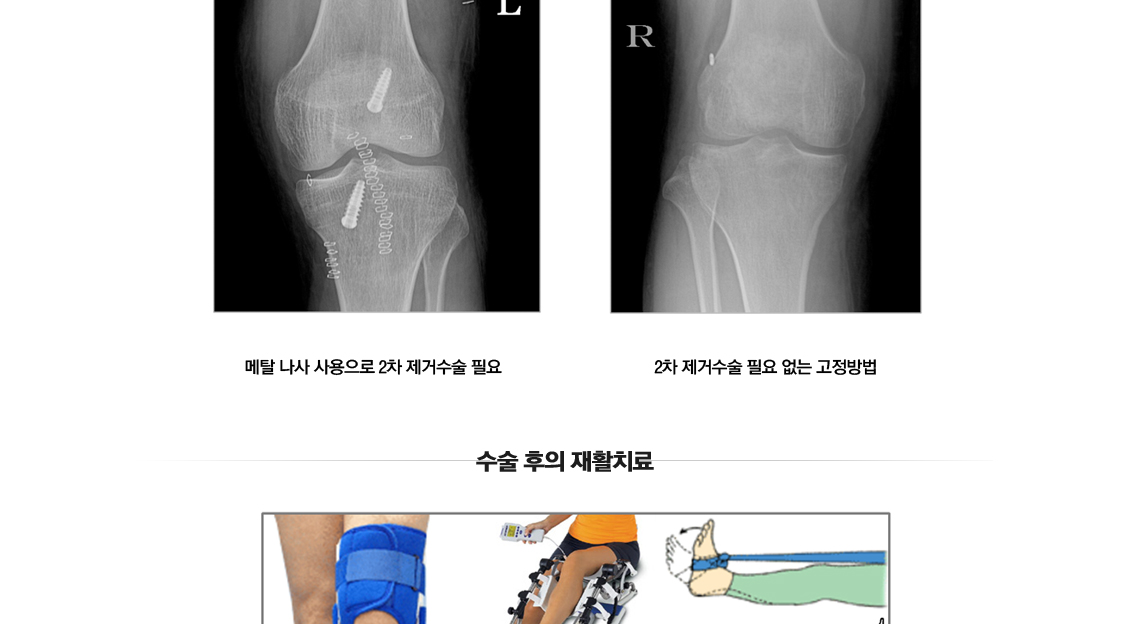

전방십자인대 재건술

무릎 골절수술